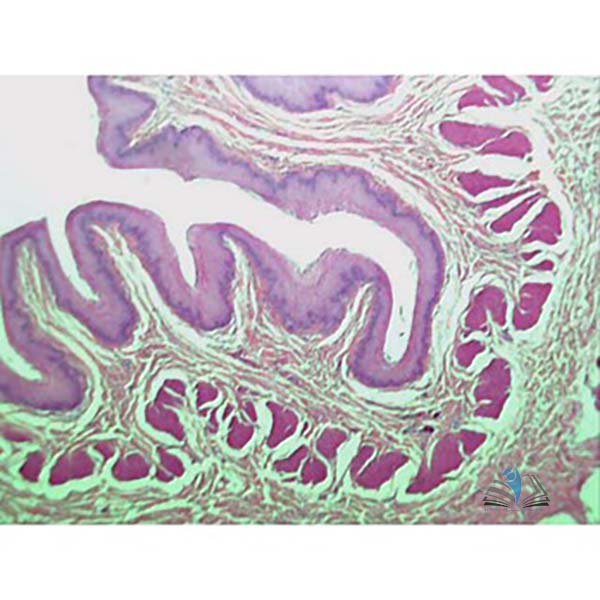

An introductory set of 5 prepared microscope slides which follow the digestive journey of food through the Human Body.

Slide set contains 1 each of the following slides:

• Small Intestine

• Colon/Large Intestine

• Tongue

• Oesophagus, general structure

• Stomach